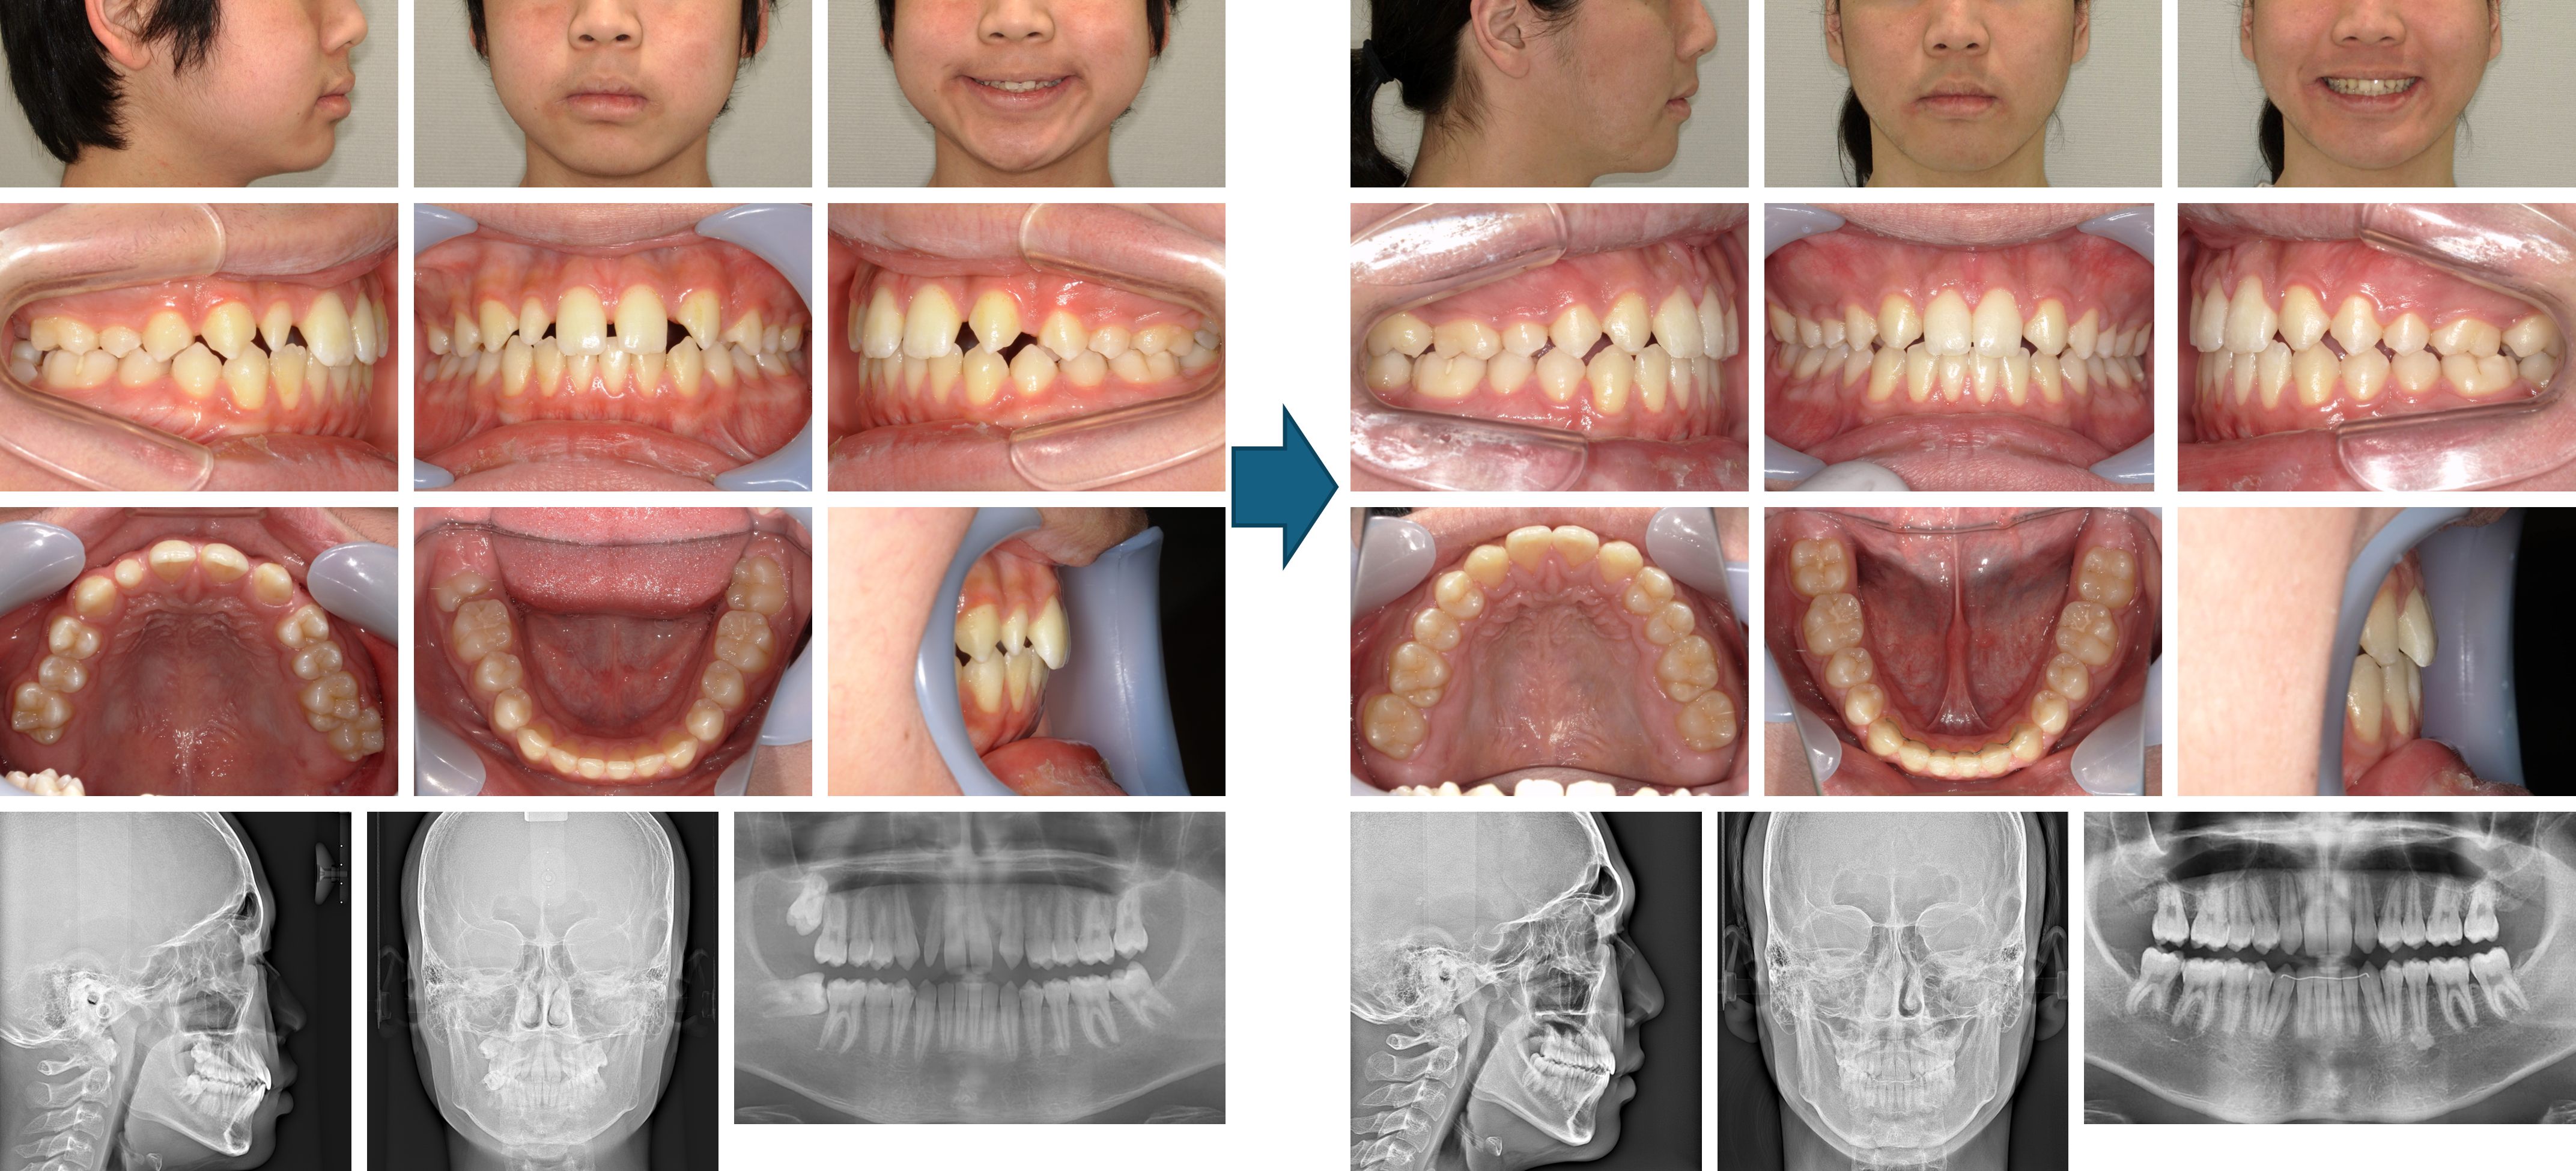

【治療例 K5284】初診時年齢:6歳11か月 / 性別:女性 / 主訴:前歯の咬み合わせ

治療の概要:第1期治療ではクワドヘリックスで側方拡大および右側中切歯の反対咬合の改善を行いながら、前方牽引装置で上顎骨の前方成長を促しました。2×4装置で上顎前歯部を綺麗に並べた後、しばらく永久歯の萌出を待ちました。側方歯の永久歯の萌出後、第2期治療では残りの永久歯にマルチブラケット装置を装着しました。綺麗な相貌と緊密な咬合を獲得しました。

主訴:前歯の咬み合わせ

診断名:上顎骨劣成長を伴う骨格性Ⅲ級、右側中切歯の反対咬合

使用した主な装置:クワドヘリックス、フェイスマスク、マルチブラケット装置、顎間ゴム

抜歯/非抜歯および抜歯部位: 非抜歯(ただし、乳歯の抜歯はあり)

治療期間:5年8か月(第1期治療:2年1か月、 第2期治療:3年7か月)

治療回数:第1期治療13回、第2期治療61回